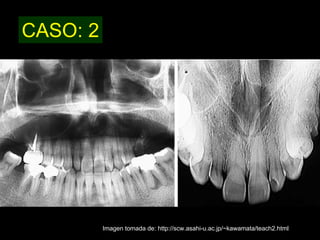

El quiste nasopalatino es un quiste embrionario situado en la línea media en la parte anterior del paladar, que se origina de los restos del conducto nasopalatino. Generalmente aparece entre los 40-60 años y se presenta como un aumento de volumen blando y no doloroso entre los incisivos centrales superiores que puede causar divergencia radicular. Las características radiográficas incluyen una lesión radiolúcida, bien delimitada y de forma redondeada u ovalada que cruza la línea media maxilar.